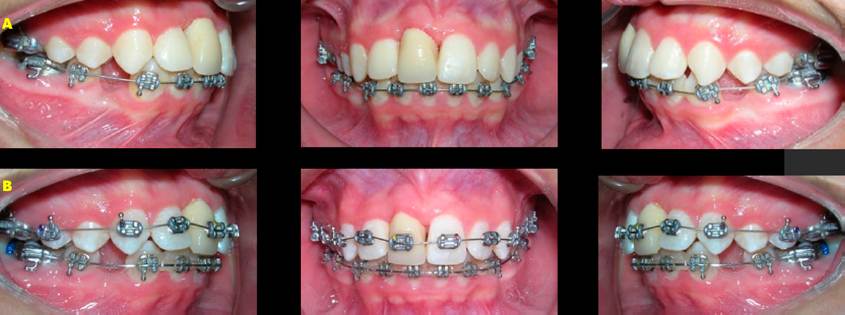

Root canal treatment was performed at week four to reduce the risk of developing complications related to pulp tissue detachment, its nerves, and vascular support24. As for occlusal refinement, this was performed by placing fixed appliances, extractions of upper first premolars, alignment, leveling, space closure, and completion of the orthodontic stage, to comply with the principles of stable occlusion and respect the esthetic demands of the patient. During appliance placement, we took care of the position of the brackets, since it is of utmost importance to provide root parallelism. Leveling and alignment is a complex process in which all crowns, including tooth 11 with a temporary crown (Figure 5) move at the same time and in different directions developing reciprocal forces between them, which can be of great help to direct the movements in our favor and thus achieve the characteristics of a natural occlusion and improve the soft tissue characteristics of the facial profile.

Figure 5 Treatment progress. A. Adjustment and placement of temporary restoration on tooth #11. B. Placement of upper appliances.

At the end of orthodontic treatment, fixed appliances were removed and retainers were placed. In panoramic radiographs and lateral head films, the periodontal and endodontic health of the transplanted tooth can be identified, as well as the root integrity.